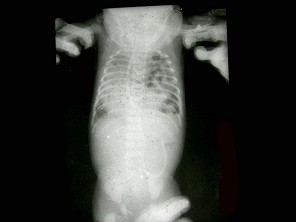

E.超声检查

男,11岁。自出生后出现活动后憋喘、口唇发紫。检查如图所示。最可能的诊断是()

A.完全性肺静脉异位引流-心下型

B.完全性肺静脉异位引流-心上型

C.完全性肺静脉异位引流-心内型

D.完全性肺静脉异位引流-混合型

E.法洛四联症